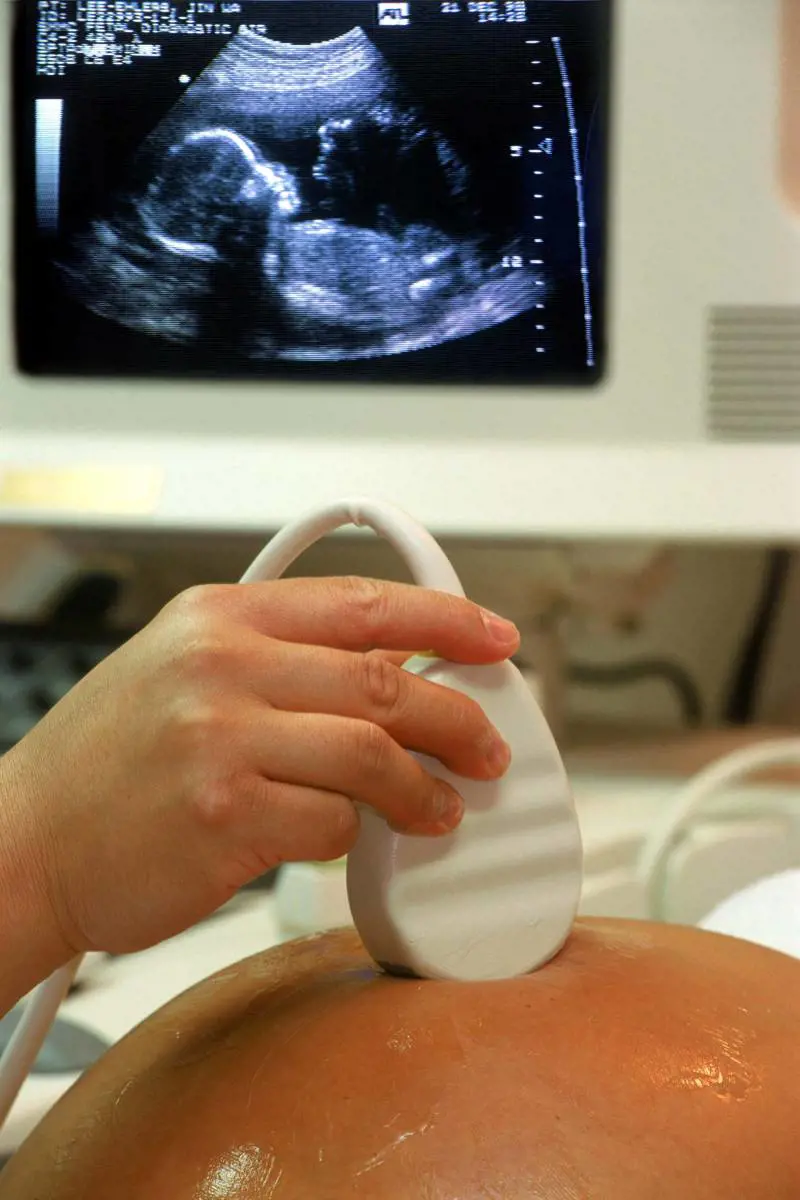

Milano - Ha salvato diversi bimbi, nonostante le scelte dei genitori andassero in direzione opposta. L’ultimo caso qualche mese fa, quando a seguito di un’interruzione volontaria di gravidanza tra la 22sima e la 23sima settimana, il bimbo è venuto alla luce dando segni di vitalità. «Siamo intervenuti, come sempre, l’abbiamo portato in terapia intensiva - spiega Antonio Boldrini, professore di neonatologia all'università di Pisa - e l'abbiamo salvato».

«Dalla amniocentesi emerge che il nascituro ha una genesia del corpo calloso, cioè una malformazione del cervello, che in alcuni casi può non avere conseguenze, in altri anche gravi. Da qui la decisione dei genitori di ricorrere all’interruzione di gravidanza, decisione che non è stata messa in dubbio neppure davanti all’evidenza che, essendo il feto tra la 23sima e 24sima settimana, avrebbe avuto il 60 per cento di possibilità di sopravvivere e che un parto prematuro avrebbe potuto arrecare ulteriori danni. Morale: il bimbo è sopravissuto senza grossi problemi all'aborto e la malformazione era innocua».